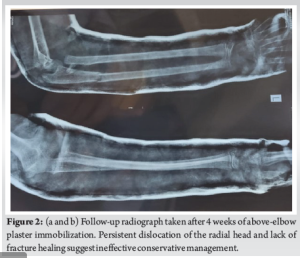

A young girl had a history of trauma to the left elbow during a school activity. The parents give a history of a fall on an outstretched hand planted firmly on the ground, suggestive of varus stress on the left elbow. There were no external wounds or distal neurovascular deficit in the upper limb. She had complaints of sudden onset pain, swelling, and restriction of movements in the left elbow. She was taken to a local hospital wherein radiographs were taken (Fig. 1) and was managed conservatively with above elbow plaster of paris application for 4 weeks (Fig. 2). She presented to our out patient department almost 1 year post the injury with complaints of pain on rest and pain at terminal flexion and extension with restriction of movements of her left elbow.

On examination, the patient had complete flexion and extension of the left elbow which was compared to the opposite side. Pain on terminal flexion and extension was noted. The patient had a reduction of pronation and supination of the left elbow compared to the opposite side. The wrist joint was duly examined and was found to be normal. Radiographs were taken of both elbow joints, and the patient was diagnosed to have a neglected left Monteggia fracture (Bado type IV) with a malunited radial head (Fig. 3).